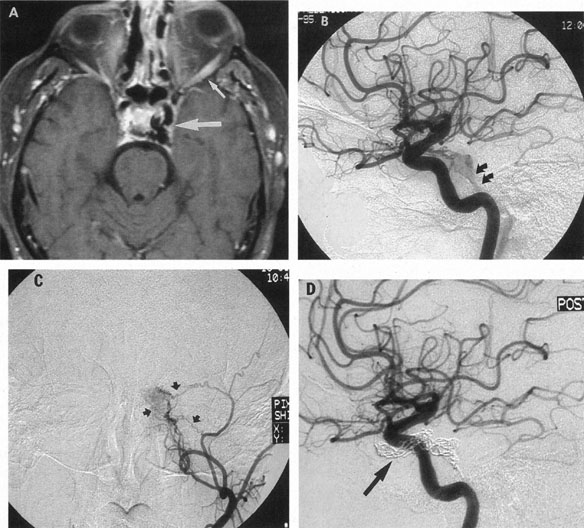

The detection of intracranial AVMs is facilitated by CT scanning and MRI (Fig. 10),88 but optimal management requires selective angiography89 that assesses the size and configuration of the mass, the number and location of feeding arteries, the flow characteristics and degree of steal from brain parenchyma, and the pattern of venous drainage.

Fig. 10. Neuroimaging of arteriovenous malformation. A: Coronal magnetic resonance imaging (MRI) (TR, 600 ms; TE, 20 ms) shows wedge-shaped vascular mass extending from the surface of the parietal cortex (white arrows) to the lateral ventricle (black arrows; asterisk, arterial feeder). B: Posteroanterior left arteriogram of the same lesion. C: Axial computed tomography scan with contrast enhancement. D: Axial MRI of a large arteriovenous malformation, first echo (TR, 2000 ms; TE, 20 ms). E: Second echo (TR, 2000 ms; TE, 90 ms). (From Smith HJ, Strother CM, Kikuchi Y, et al: MR imaging in the management of supratentorial intracranial AVMS. AJNR Am J Neuroradiol 9:225, 1988.)